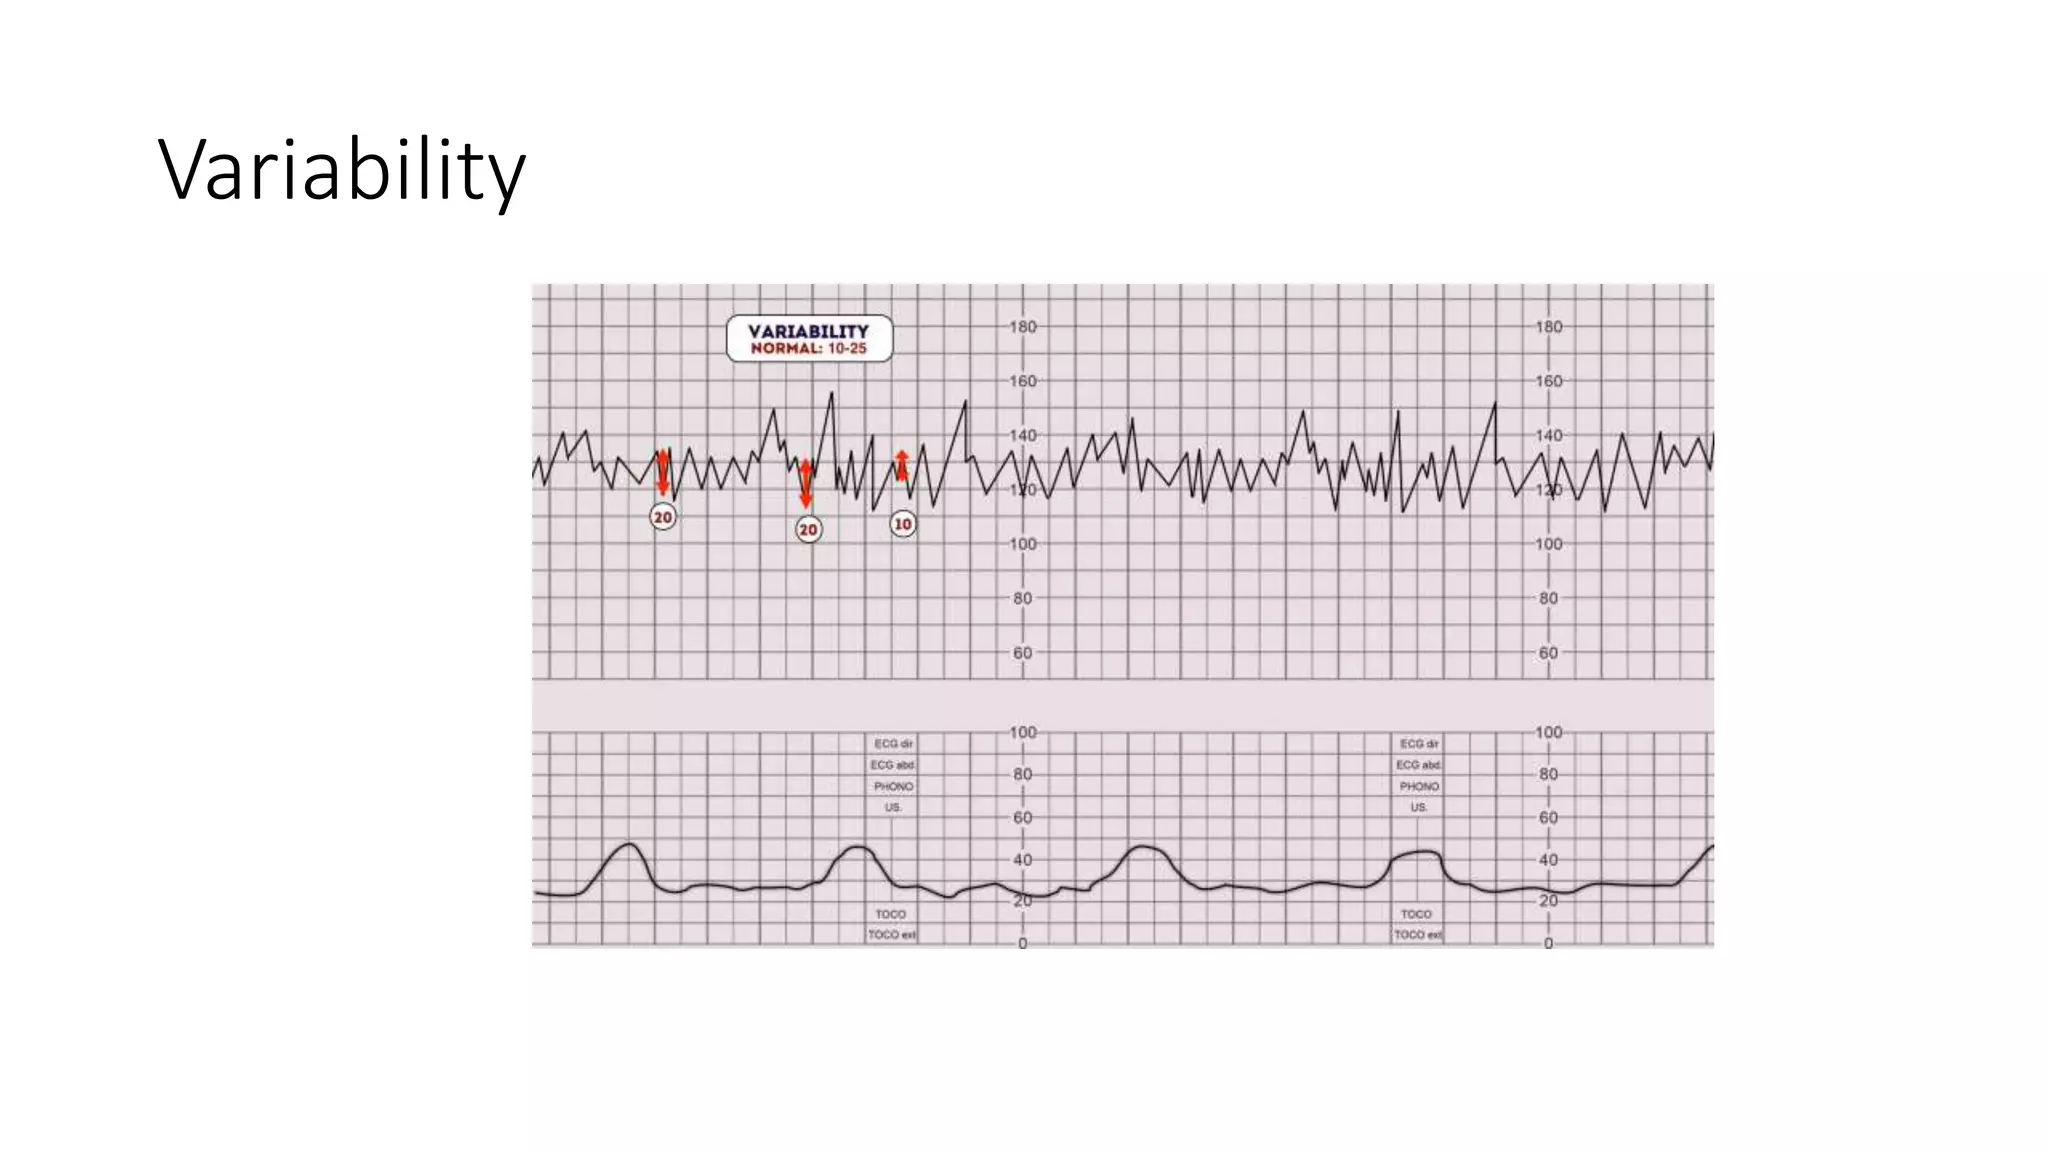

The document discusses key metrics for monitoring a baby's heart rate in utero, including the normal baseline rate of 100-160 bpm and variability. It also covers types of accelerations and decelerations that can occur, such as early or late, as well as bradycardia, which is an abnormally slow heart rate.